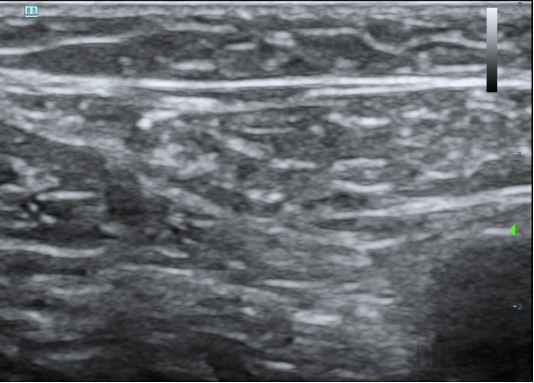

本次臨床試驗(yàn)的入組患者為63歲男性,其靜脈曲張符合本臨床試驗(yàn)方案入選入排標(biāo)準(zhǔn)。經(jīng)上海交通大學(xué)醫(yī)學(xué)院附屬第九人民醫(yī)院陸信武主任團(tuán)隊(duì)對(duì)患者評(píng)估,選擇使用恩盛醫(yī)療自主研發(fā)的VeSeal靜脈閉合系統(tǒng),在超聲影像的引導(dǎo)下采用微創(chuàng)介入的方式將病變血管閉合,整個(gè)手術(shù)時(shí)間不到半小時(shí)。

據(jù)介紹,VeSeal靜脈閉合系統(tǒng)不同于其他臨床研究,VeSeal還配備了輸送導(dǎo)絲及導(dǎo)管鞘管等標(biāo)準(zhǔn)配件,注射導(dǎo)管在超聲下實(shí)時(shí)可見(jiàn),鞘管具有標(biāo)尺,手術(shù)過(guò)程無(wú)需其它配件,方便臨床醫(yī)生快速、便捷、高效的將病變血管閉合。

1、開(kāi)發(fā)整套靜脈閉合系統(tǒng),手術(shù)操作精準(zhǔn)、便捷。整套系統(tǒng)可有效避免醫(yī)生在手術(shù)時(shí)進(jìn)行單個(gè)產(chǎn)品匹配,便于醫(yī)生手術(shù)操作,提高臨床效率。其輸送配件在超聲定位下實(shí)時(shí)可見(jiàn),導(dǎo)管鞘具有刻度,可在手術(shù)過(guò)程進(jìn)行實(shí)時(shí)參考,實(shí)現(xiàn)精準(zhǔn)注膠。另外,整套系統(tǒng)采用精心設(shè)計(jì)的外觀包裝,依照國(guó)內(nèi)醫(yī)生的習(xí)慣,量身定制、使用方便、易于操作。 2、靜脈閉合劑粘度更高,閉合效率更好。VeSeal靜脈閉合系統(tǒng),具備更強(qiáng)大粘合度,并保持良好的柔韌性,固化時(shí)間可控,實(shí)現(xiàn)靜脈血管更好的封閉效果,降低疾病的復(fù)發(fā)率。 3、靜脈閉合劑統(tǒng)一采取裝置規(guī)格,用量可供雙腿治療,更符合臨床需求,減少患者手術(shù)費(fèi)用。 4、電動(dòng)注射器替代一次性手持泵,減少昂貴的手術(shù)費(fèi)用。研發(fā)設(shè)計(jì)自動(dòng)注射系統(tǒng),可實(shí)現(xiàn)閉合劑的人機(jī)交互式自動(dòng)注射,1人即可完成手術(shù),避免因術(shù)者失誤造成的不良事件。通過(guò)開(kāi)發(fā)閉合劑的定量定時(shí)注射系統(tǒng),恩盛醫(yī)療可將靜脈曲張的閉合治療實(shí)現(xiàn)自動(dòng)化,完全借助機(jī)器實(shí)現(xiàn)。 5、VeSeal安全無(wú)毒、生物相容性好,能瞬間將血管閉合,關(guān)閉靜脈,后期血管逐漸肌化,從而徹底治愈靜脈曲張。